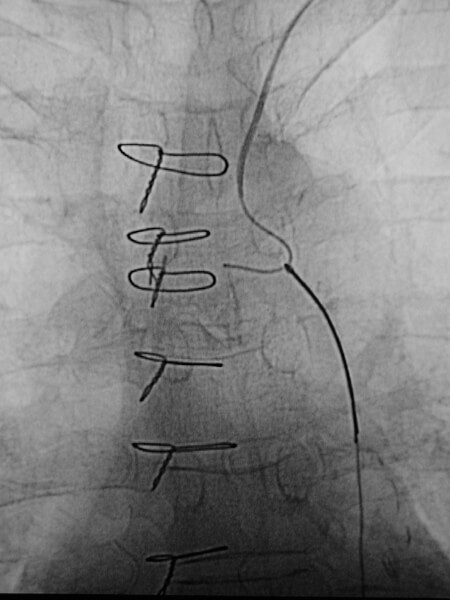

Early image from a thoracic aortogram demonstrating occlusion of the left subclavian artery. -